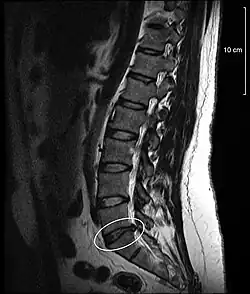

Die Protrusion zeigt im Gegensatz zum Bandscheibenvorfall in der Sagittalebene im MRT-Bild einen craniocaudalen Durchmesser, der kleiner oder gleich der Höhe der Bandscheibe ist.[2]